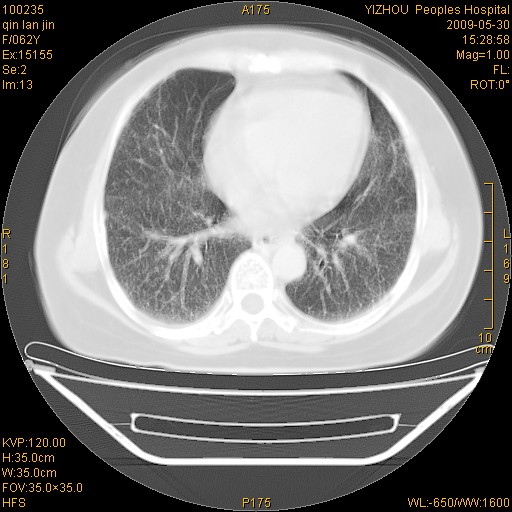

标题: CT20268:肺泡癌?间质性肺炎? [打印本页]

标题: CT20268:肺泡癌?间质性肺炎?

女,62岁,近二年经常咳嗽,近二个月,消瘦、乏力。

弥漫性双肺间质纤维化。

两肺弥漫性间质性病变(间质性肺炎伴肺间质纤维化?)。

弥漫性双肺间质纤维化

支持弥漫性肺间质纤维化。

间质性肺炎伴肺间质纤维化。

纵隔淋巴结大,须排外癌性淋巴管炎